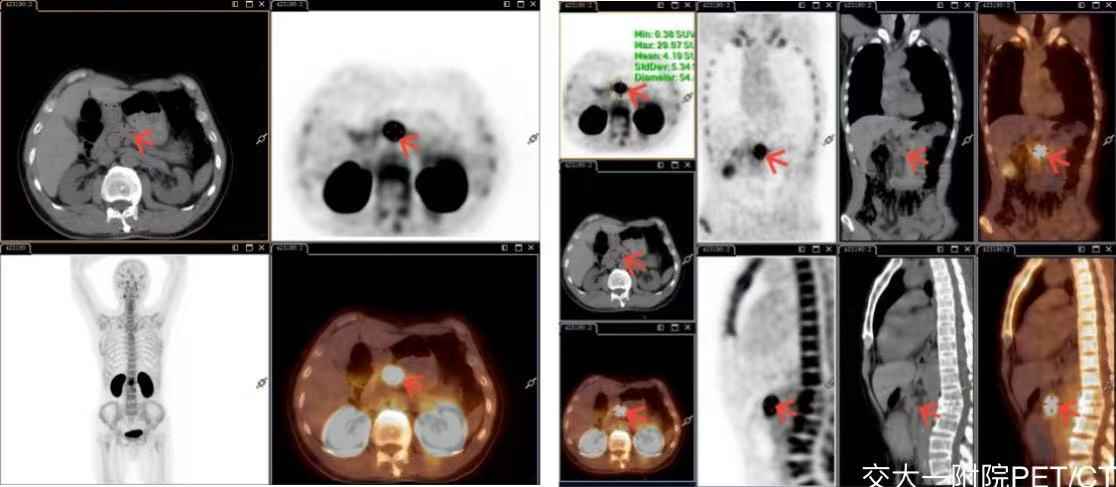

病例1 男,59岁,反复晕厥、癫痫发作,严重低血糖,外院提示胰颈占位,18F-Exendin-4 PET/CT 清晰显示病变GLP-1 受体表达显著增高,明确诊断胰岛素瘤,为手术切除提供精准影像导航。